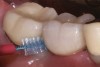

Fig 8. Adequate space has been provided to permit insertion of an interdental brush mesial and distal to implant site No. 30.

Figure 8